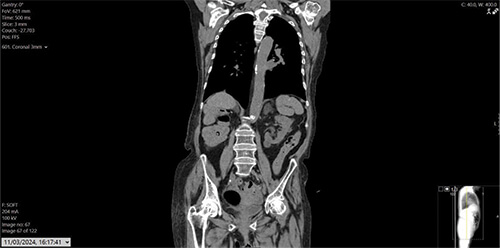

Figure 3: CT CAP, status post right radical nephrectomy. Left simple lower pole renal cyst.

Blood work reported estimated glomerular filtration rate (eGFR) of 26, creatinine 161, and normal liver functions tests (LFTs). The CT at initial presentation with renal cancer and the recent contrast CT chest, abdomen and pelvis are shown in Figures 1-3. MRI of the skull reported a 3.3x2.3cm soft tissue heterogeneous lesion involving the parietal bone and invading the dura (Figure 4). Ultrasound-guided scalp biopsy showed infiltration of fibrous tissue by sheets of epithelioid tumour cells with abundant clear cytoplasm and intervening prominent blood vessels. The tumour cells expressed RCC, CD10 and PAX 8. They did not express CK7, CK20, TTF-1, Gata3 and WT-1. The conclusion was metastatic RCC.